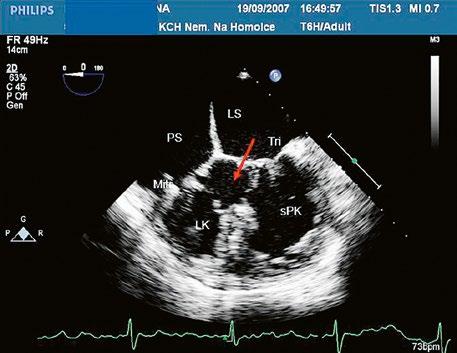

z Kompletní atrioventrikulární septální defekt (Obr. 45.14, Video 45.11, Video 45.12): chybí dolní část síňového septa a vtoková část komorového septa (nerestriktivní vtokový komorový defekt), je přítomna komunikace mezi oběma síněmi i oběma komorami, atrioventrikulární chlopeň bývá společná, většinou pěticípá.

z Přechodná forma atrioventrikulárního septálního defektu: (Obr. 45.15) komunikace mezi síněmi defektem typu primum, restriktivní defekt komorového septa při částečném spontánním uzávěru komorové složky defektu, oddělené mitrální a trikuspidální ústí, „rozštěp“ předního cípu mitrální chlopně.

Obr. 45.14 TTE, čtyřdutinová apikální projekce. Kompletní atrioventrikulární septální defekt je označen křížky, představuje komunikaci mezi oběma síněmi i komorami se společnou atrioventrikulární chlopní (AVch)

LK – levá komora, LS – levá síň, PK – pravá komora, PS – pravá síň

Obr. 45.15 Přechodná forma atrioventrikulárního septálního defektu, TEE, čtyřdutinová projekce. V dolní části síňového septa je mezi pravou síní (PS) a levou síní (LS) velká komunikace typu ostium primum (označená šipkou), původní komorová složka defektu (označená hvězdičkou) je částečně spontánně uzavřena závěsným aparátem trikuspidální chlopně.